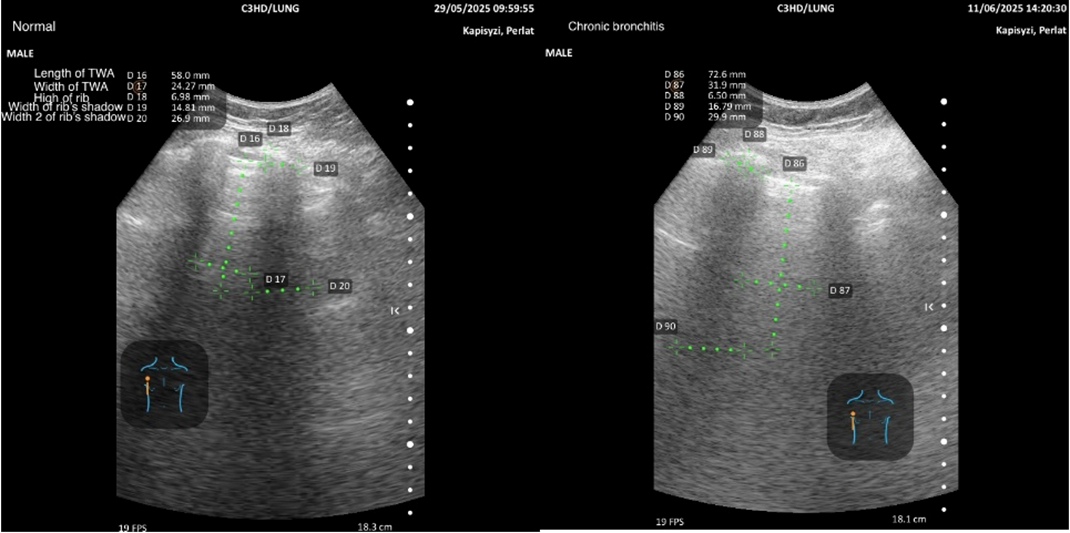

The overall project is structured in three complementary parts: (1) echographic features of emphysema compared with normal subjects, (2) chronic bronchitis compared with normal subjects (the focus of the present manuscript), and (3) emphysema versus chronic bronchitis. Representative examples of measurements by region, together with pictograms, are presented to illustrate the methodology.

The methodology for quantifying regional variables in normal subjects and bronchitis patients is illustrated with pictograms and representative examples